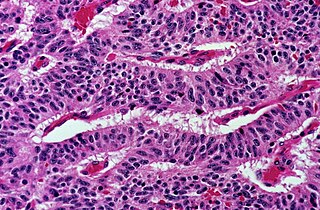

The most commonly used stain in histology is a combination of hematoxylin and eosin (often abbreviated H&E). Hematoxylin is used to stain nuclei blue, while eosin stains the cytoplasm and the extracellular connective tissue matrix of most cells pink. There are hundreds of various other techniques which have been used to selectively stain cells. Other compounds used to color tissue sections include safranin, Oil Red O, congo red, silver salts and artificial dyes. Histochemistry refers to the science of using chemical reactions between laboratory chemicals and components within tissue. A commonly performed histochemical technique is the Perls' Prussian blue reaction, used to demonstrate iron deposits in diseases like Hemochromatosis.[2]

Architectural pattern of any suspicious cells, in this case nests of cells, as well as components of the intervening stroma.

Papillary: Protuberances of epithelioid cells around fibrovascular cores.